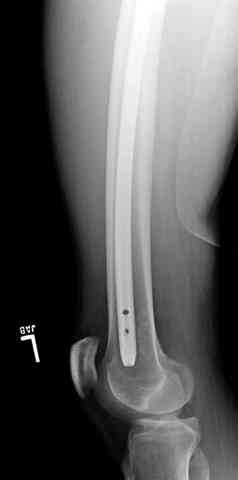

Для фиксации огнестрельных переломов бедра и длинных костей предпочтение отдаем интрамедуллярному методу фиксации, о котором еще в 1993 году написали Bergman M. Tornetta P. Kerina M. Sandhu H. Simon G. Deysine G. Journal of Trauma. [JC:kaf] 34(6):783-5

1 Проксимальный перелом бедра, антеградный гвоздь